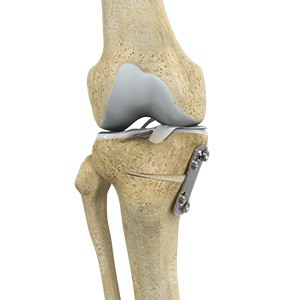

Knee Osteotomy

nee osteotomy is a surgical procedure in which the upper part of shinbone (tibia) or lower part of thighbone (femur) is cut and realigned. It is usually performed in arthritic conditions affecting only one side of your knee. The aim is to take the pressure off the damaged area and shift it to the other side of your knee with healthy cartilage.